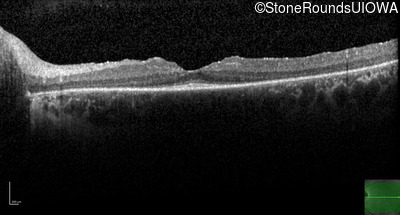

Optical Coherence Tomography - Left -

20/20

Exemplar / OCT Stack